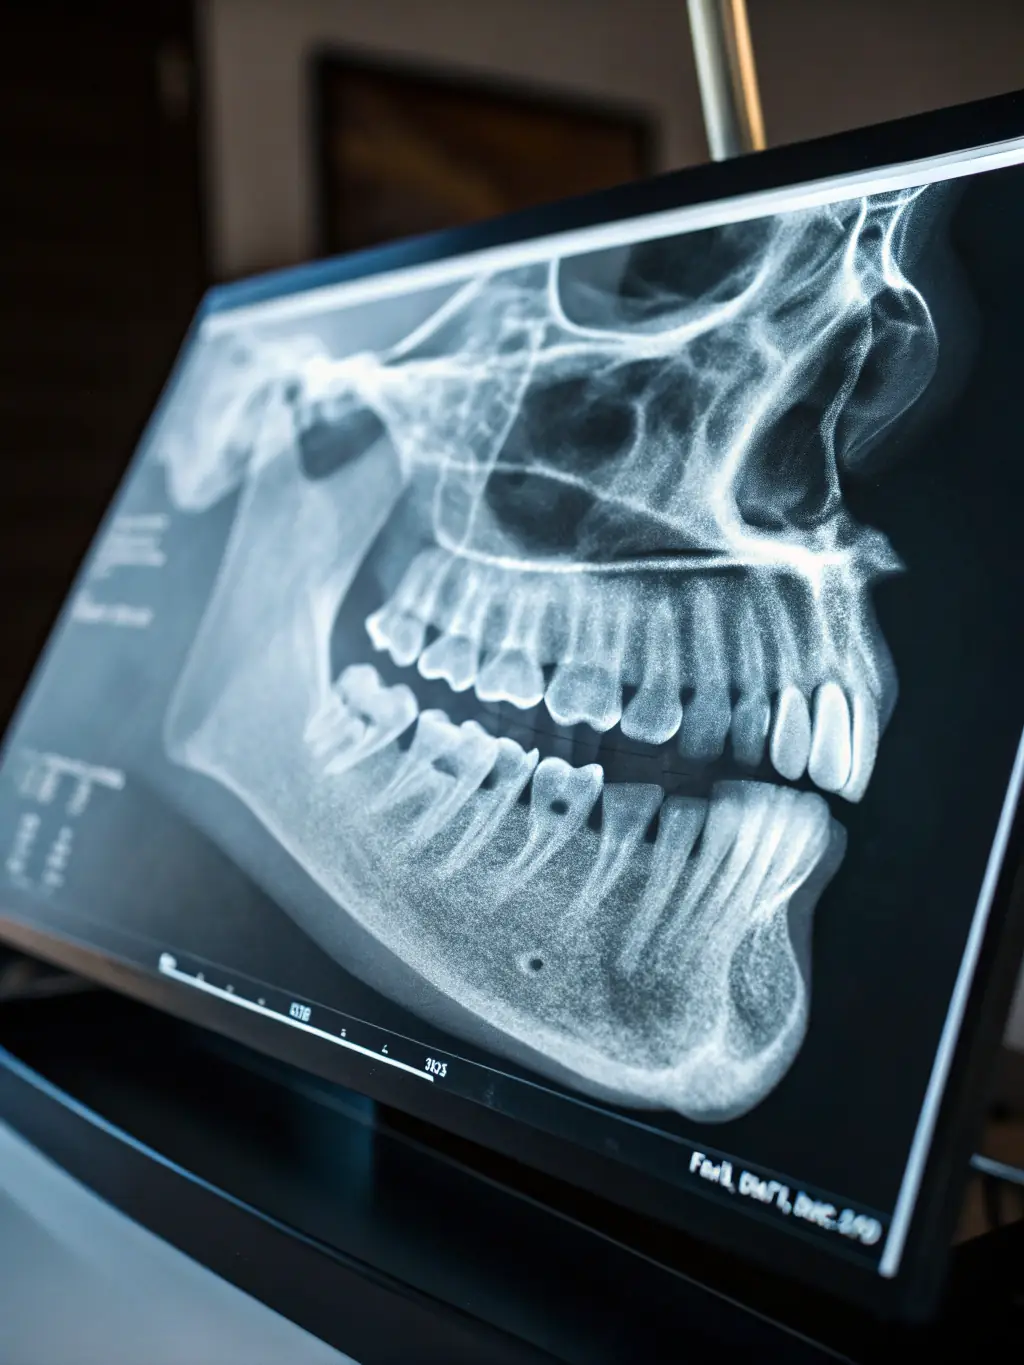

A close-up, detailed x-ray image showing impacted wisdom teeth pressing against the adjacent molars, causing visible crowding and potential damage. The image is professionally taken and highlights the need for extraction.

Preventing Future Dental Problems

Impacted wisdom teeth can lead to crowding, cysts, and damage to nearby teeth. Early removal prevents these issues, ensuring a healthier smile. Our team at Joshua Dental is here to help.